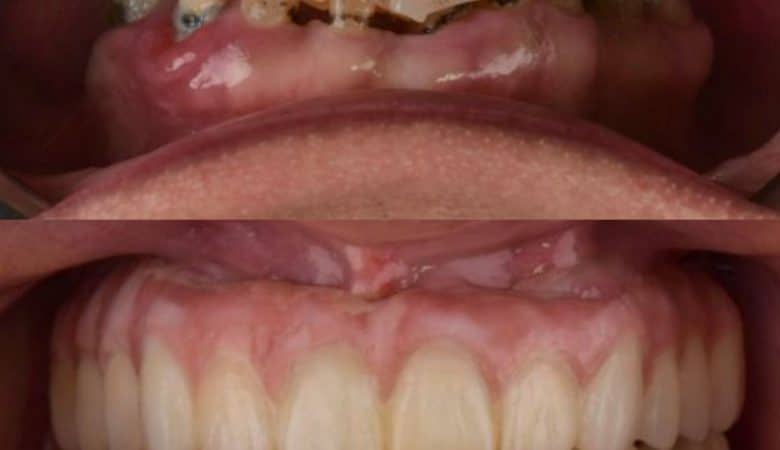

Technique: Socket Shield

Below is a case of full arch same day temporization using the socket shield , root submergence and pontic shield techniques to preserve the site architecture . Neodent GM implants were placed in a guided fashion and same day temporization…